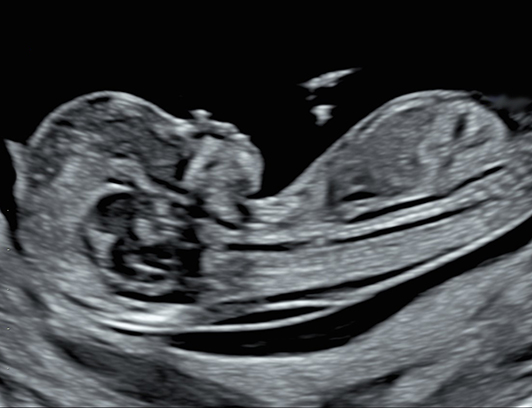

Obstetriska Ultraljudsundersökningar för alla gravida kvinnor

Alla erbjuds en ultraljudsundersökning både i vecka 11-14 samt under vecka 18-20.

Dessa undersökningar skall visa graviditetslängden, tidpunkt för beräknad förlossning samt hur graviditeten utvecklas.